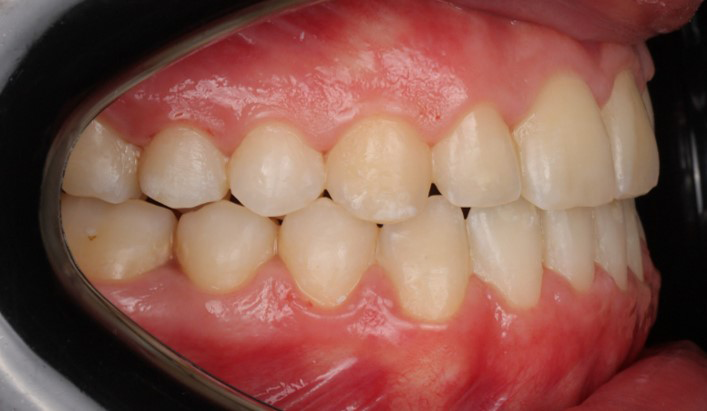

A 22-year-old female patient presented with a Class III malocclusion. She does not like her own profile. Her facial profile was straight with a slightly retrusive maxilla, the upper incisors were within normal inclination, and the lower incisors were retroclined. Bolton discrepency is on mandible for 6 teeth. A retruded upper lip and a normally positioned lower lip were noted. There was also a marked lack of midface support, and the constricted dental arches resulted in a narrow smile and pronounced dark buccal corridors.

At the end of treatment, the patient’s occlusion was corrected to Class I molar and canine relationships with a physiological overjet and overbite. Irregularities in both arches were eliminated, arch forms were coordinated, and incisor torque was effectively controlled to position the roots centrally within the alveolar bone, enhancing stability. Satisfactory intercuspation was achieved in both the anterior and posterior segments, with maintenance of midline coincidence and periodontal health throughout treatment. The case was finished and transitioned into the retention phase using fixed retainers in the maxillary and mandibular anterior regions.